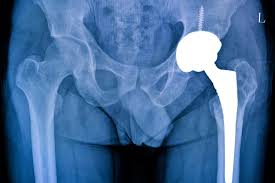

Hip damage usually develops due to arthritis, avascular necrosis, fractures, or long-term joint wear. As a result, patients experience pain, stiffness, and limited movement. Over time, walking and sitting become difficult. Therefore, hip replacement becomes necessary when medications and therapy no longer help. At Varunam Super Speciality Hospital, early diagnosis allows timely surgical planning under Ayushman Bharat coverage.

Varunam Super Speciality Hospital follows modern surgical protocols for hip replacement. Therefore, patients benefit from precise surgical techniques, safe anesthesia, and infection-controlled operation theatres. Additionally, advanced implants improve joint stability and durability. Under the leadership of Dr. Utsav Agrawal, every procedure focuses on safety, alignment accuracy, and long-term joint function.

Varunam Super Speciality Hospital in Mandla provides free hip replacement surgery under the Ayushman Bharat scheme for eligible patients, ensuring advanced orthopedic care without financial burden. The hospital combines experienced orthopedic surgeons, modern surgical techniques, and patient-focused care to deliver safe and effective hip replacement procedures.

Equipped with advanced operation theatres, digital imaging systems, and dedicated rehabilitation facilities, Varunam ensures accurate implant placement and improved joint function. The hospital supports cashless and free treatment under Ayushman Bharat, along with structured pre-operative assessment and post-operative physiotherapy, making it a trusted center for free hip replacement Ayushman Bharat in Mandla.